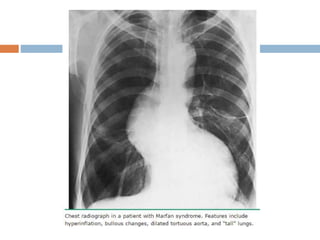

 Pulmonary disease — Some patients develop

emphysematous changes with lung bullae predominantly in

the upper lobes, can predispose to spontaneous

pneumothorax

 Initial investigations

 Echocardiography, thorax CT, and thorax MRI are used

initially for aortic root imaging.

 Abdominal ultrasound, CT, and MRI are used for

visualisation of the descending aorta.

 CXR is performed to exclude the presence of a

pneumothorax, and may reveal emphysematous bullae.